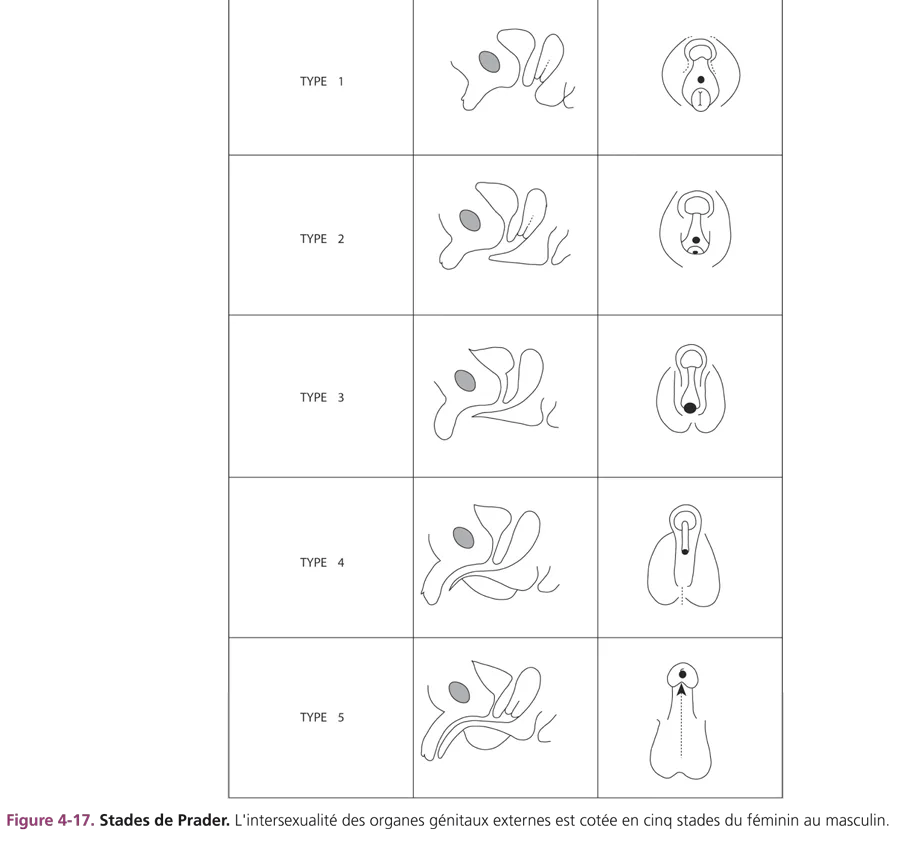

Leur diagnostic se pose à la période néonatale devant un enfant présentant une malformation des organes génitaux externes. Cette situation clinique impose un diagnostic étiologique rapide et une évaluation des possibilités de chirurgie réparatrice afin d’envisager le choix du sexe. L’examen clinique constate un développement plus ou moins marqué du bourgeon génital, la présence d’un ou de deux orifices périnéaux, la topographie plus ou moins postérieure de l’hypospade et la soudure plus ou moins complète des bourrelets labioscrotaux dans lesquels on peut palper des gonades. Le degré de différenciation des organes génitaux externes est coté selon les stades de Prader (fig. 4-17).